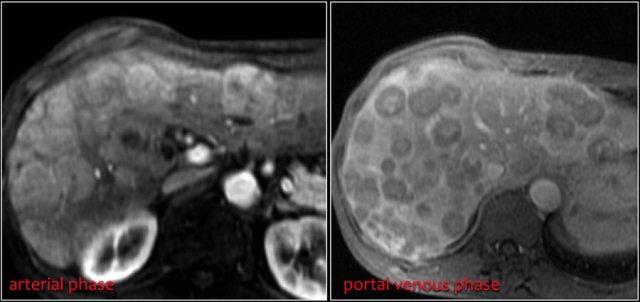

Di căn gan thường có tính chất tăng sinh mạch và có thể có hoại tử trung tâm.

Cùng bệnh nhân.

Bốn năm sau lần chụp CT ban đầu, ghi nhận nhiều tổn thương di căn gan.

Lưu ý kiểu ngấm thuốc tăng sinh mạch trong thì động mạch muộn.